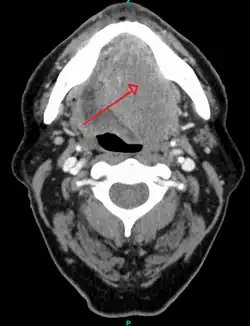

A large head and neck squamous-cell carcinoma of the tongue as seen on CT imaging

About 90%[4] of cases of head and neck cancer (cancer of the mouth, nasal cavity, nasopharynx, throat and associated structures) are due to SCC.